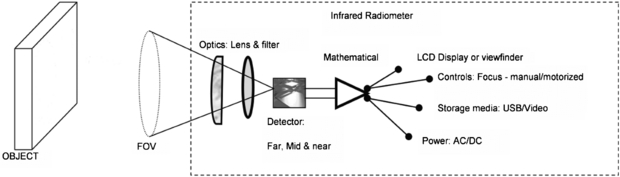

2.3.2. Thermal imager specifications and quality assurance

Figure 10 shows a schematic for a typical thermal imager design. Incident radiation is focussed by a filter and lens arrangement onto the surface of an infrared detector system. This may consist of a single detector which is mechanically scanned across the field of view by a system of rotating mirrors or, more commonly in modern devices, it may comprise a large collection of 'staring' infrared detectors fabricated onto a single microchip. In this case there is a one-to-one correspondence between each detector on the array and each pixel within the output thermal image. Such detectors are termed focal plane arrays (FPAs) because the readout circuitry is incorporated onto the detector chip to provide complete processing of the image in the focal plane.

Figure 10. Schematic of a thermal imager (permission granted to re-use from Ring et al 2009 Sensors for Medical Thermography and Infrared Radiation Measurements (New York: Momentum)).

Download figure:

Standard image High-resolution imageThere is a wide variety of detectors available, which can operate in the 'far' (7.5–15 µm), 'mid' (2–5.6 µm) or 'near' (0.8–2 µm) thermal infrared wavebands. 'Photon' type detectors are doped semiconductors, with a current generated when infrared photons impinge on the detector and excite electrons across an energy gap. Such detectors require cooling to reduce noise (which complicates the imager design), but benefit from high thermal sensitivity. A less expensive solution is the uncooled microbolometer detector. Here, each detector in the array is heated by incident infrared radiation, causing a change in resistance. These detectors are typically of lower thermal sensitivity than their cooled counterparts, and are more prone to drift with change in ambient temperature. Nonetheless, refinements in design and fabrication have seen a radical improvement in uncooled detector performance in recent years.